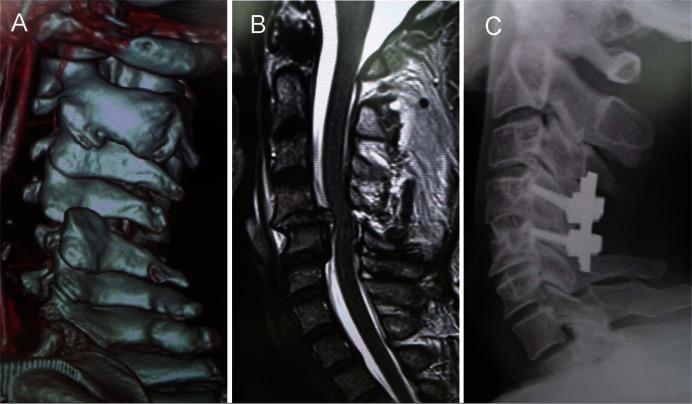

Significant progress has been made in image-guided surgery (IGS) over the last few decades. IGS can be effectively applied to spinal instrumentation surgery. In the present study, we focused our attention on the feasibility and safety of image-guided spine stabilization for traumatic or osteoporotic spine injury. The IGS spine fixation with or without minimally invasive surgery (MIS) techniques such as percutaneous screw placement, balloon kyphoplasty (BKP), or vertebroplasty (VP) were accomplished in 80 patients with traumatic or osteoprotic spine injury between 2007 and 2015. The injured vertebral levels included the following: cervical spine, 41; thoracic spine, 22; and lumbar spine, 17. Neurological condition before and after surgery was assessed using the American Spinal Injury Association Impairment Scale (AIS). A total of 419 pedicle, lateral mass, or laminar screws were placed, and 399 screws (95.2%) were found to be placed correctly based on postoperative computed tomography scan. Although 20 screws (4.8%) were found to be unexpectedly placed incorrectly, no neural or vascular complications closely associated with screw placement were encountered. Neurological outcomes appeared to be acceptable or successful based on AIS. The IGS is a promising technique that can improve the accuracy of screw placement and reduce potential injury to critical neurovascular structures. The integration of MIS and IGS has proved feasible and safe in the treatment of traumatic or osteoporotic spine injury, although a thorough knowledge of surgical anatomy, spine biomechanics, and basic technique remain the most essential aspects for a successful surgery.

在过去几十年里,图像引导手术(IGS)取得了重大进展。IGS可有效应用于脊柱内固定手术。在本研究中,我们重点关注图像引导下脊柱稳定术治疗创伤性或骨质疏松性脊柱损伤的可行性和安全性。2007年至2015年间,对80例创伤性或骨质疏松性脊柱损伤患者实施了采用或不采用诸如经皮螺钉置入、球囊后凸成形术(BKP)或椎体成形术(VP)等微创手术(MIS)技术的IGS脊柱固定术。损伤的椎体节段包括:颈椎41个;胸椎22个;腰椎17个。使用美国脊髓损伤协会损伤量表(AIS)评估手术前后的神经状况。共置入419枚椎弓根、侧块或椎板螺钉,根据术后计算机断层扫描,发现399枚螺钉(95.2%)置入正确。尽管发现20枚螺钉(4.8%)意外置入错误,但未遇到与螺钉置入密切相关的神经或血管并发症。基于AIS,神经学结果似乎是可接受的或成功的。IGS是一种有前景的技术,可提高螺钉置入的准确性并减少对关键神经血管结构的潜在损伤。尽管对手术解剖学、脊柱生物力学和基本技术的透彻了解仍然是成功手术的最关键方面,但MIS与IGS的结合已被证明在治疗创伤性或骨质疏松性脊柱损伤方面是可行和安全的。